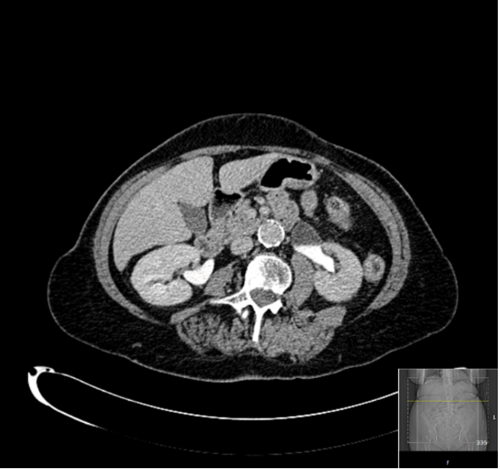

A 74-year-old had an ultrasound scan arranged by her GP demonstrating left-sided hydronephrosis. A retrograde study revealed a narrowed upper ureter. An attempt at ureteroscopy resulted in a perforation and extravasation, so was abandoned and a CT urogram was requested (Figure 1).

Figure 1: CT urogram suggesting a possible left PUJO.

This, and a subsequent MAG 3 renogram (Figure 2), were suggestive of a pelviureteric junction (PUJ) obstruction. However, given the history of haematuria and lifelong smoking and the finding from the retrograde, it was decided to repeat an attempt at direct visualisation to exclude a transitional cell carcinoma (TCC) before planning a pyeloplasty.